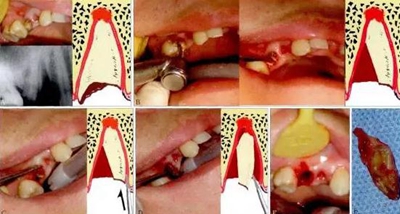

1.jpg

圖1 斜面原理。阻生的47已造成46遠中牙根部分吸收(a),手術(shù)入路較為狹小而受限(b)。為了解除47脫位阻力,對牙體進行分割(c)。將47牙切割成A和B,A部分因斜面(s)的存在可沿藍色箭頭方向順利脫位,并為B部分的松解創(chuàng)造空間,松解

后的B部分可通過多次分割取出(d)。如此可以盡量減少開窗去骨量,多保留鄰牙頸緣的骨質(zhì)(白色箭頭)。α:內(nèi)摩擦角;L:舌側(cè)。

2.jpg

圖2 榫楔原理。雙側(cè)阻生的上頜尖牙已導(dǎo)致雙側(cè)中切牙嚴重牙根吸收(a),為了避免在拔牙過程中對中切牙的擠壓,分割牙體時,按圖b中所示,將中間一段切割為上大下小的楔形(W),可以無阻力去除,然后再去除兩端的牙體(c),從而在最大

程度上保護了中切牙。在術(shù)后6月隨訪時,雙側(cè)中切牙已經(jīng)穩(wěn)固,其根尖部位骨質(zhì)恢復(fù)良好(d)。